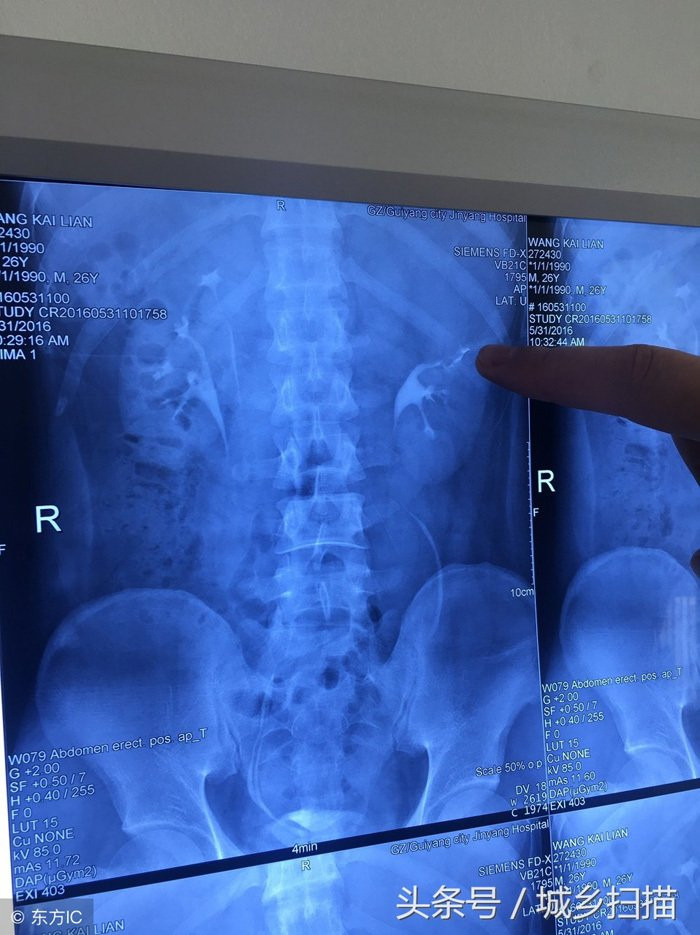

Vương Khai Luyện một lần bị đau dữ dội ở phần lưng eo, vì không chịu nổi mới đến bệnh viện kiểm tra. Sau khi kiểm tra, chụp X quang các bác sĩ phát hiện anh Vương có 4 quả thận.

Kết quả chụp X-quang khiến bác sĩ phải bất ngờ

Vương Khai Luyện có 4 quả thận. Hai quả thận ở mỗi bên dài như một em bé dính liền. Thận của một người thường có kích thước tương đương với nắm tay của người đó. Bốn quả thận của Vương Khai Luyện nhỏ hơn người bình thường và chỉ bằng cỡ nắm tay của em bé.